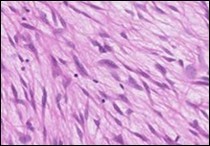

The neoplasm frequently infiltrates abutting skeletal muscle. Occasionally, tumefaction denominates hyper-cellular foci, tumour necrosis, cellular or nuclear atypia and mitotic figures, features which are characteristic of intermediate to high grade sarcoma. Localized tumour reoccurrence may be hyper-cellular with enhanced mitotic activity 4, 5. On ultrastructural examination, fibroblastic differentiation is exemplified 5. Figure 1, Figure 2, Figure 3, Figure 4, Figure 5, Figure 6, Figure 7, Figure 8.

Figure 1.Low grade fibromyxoid sarcoma enunciating fibrous and myxoid zones of uniform spindle-shaped tumour cells with absence of atypia 9.